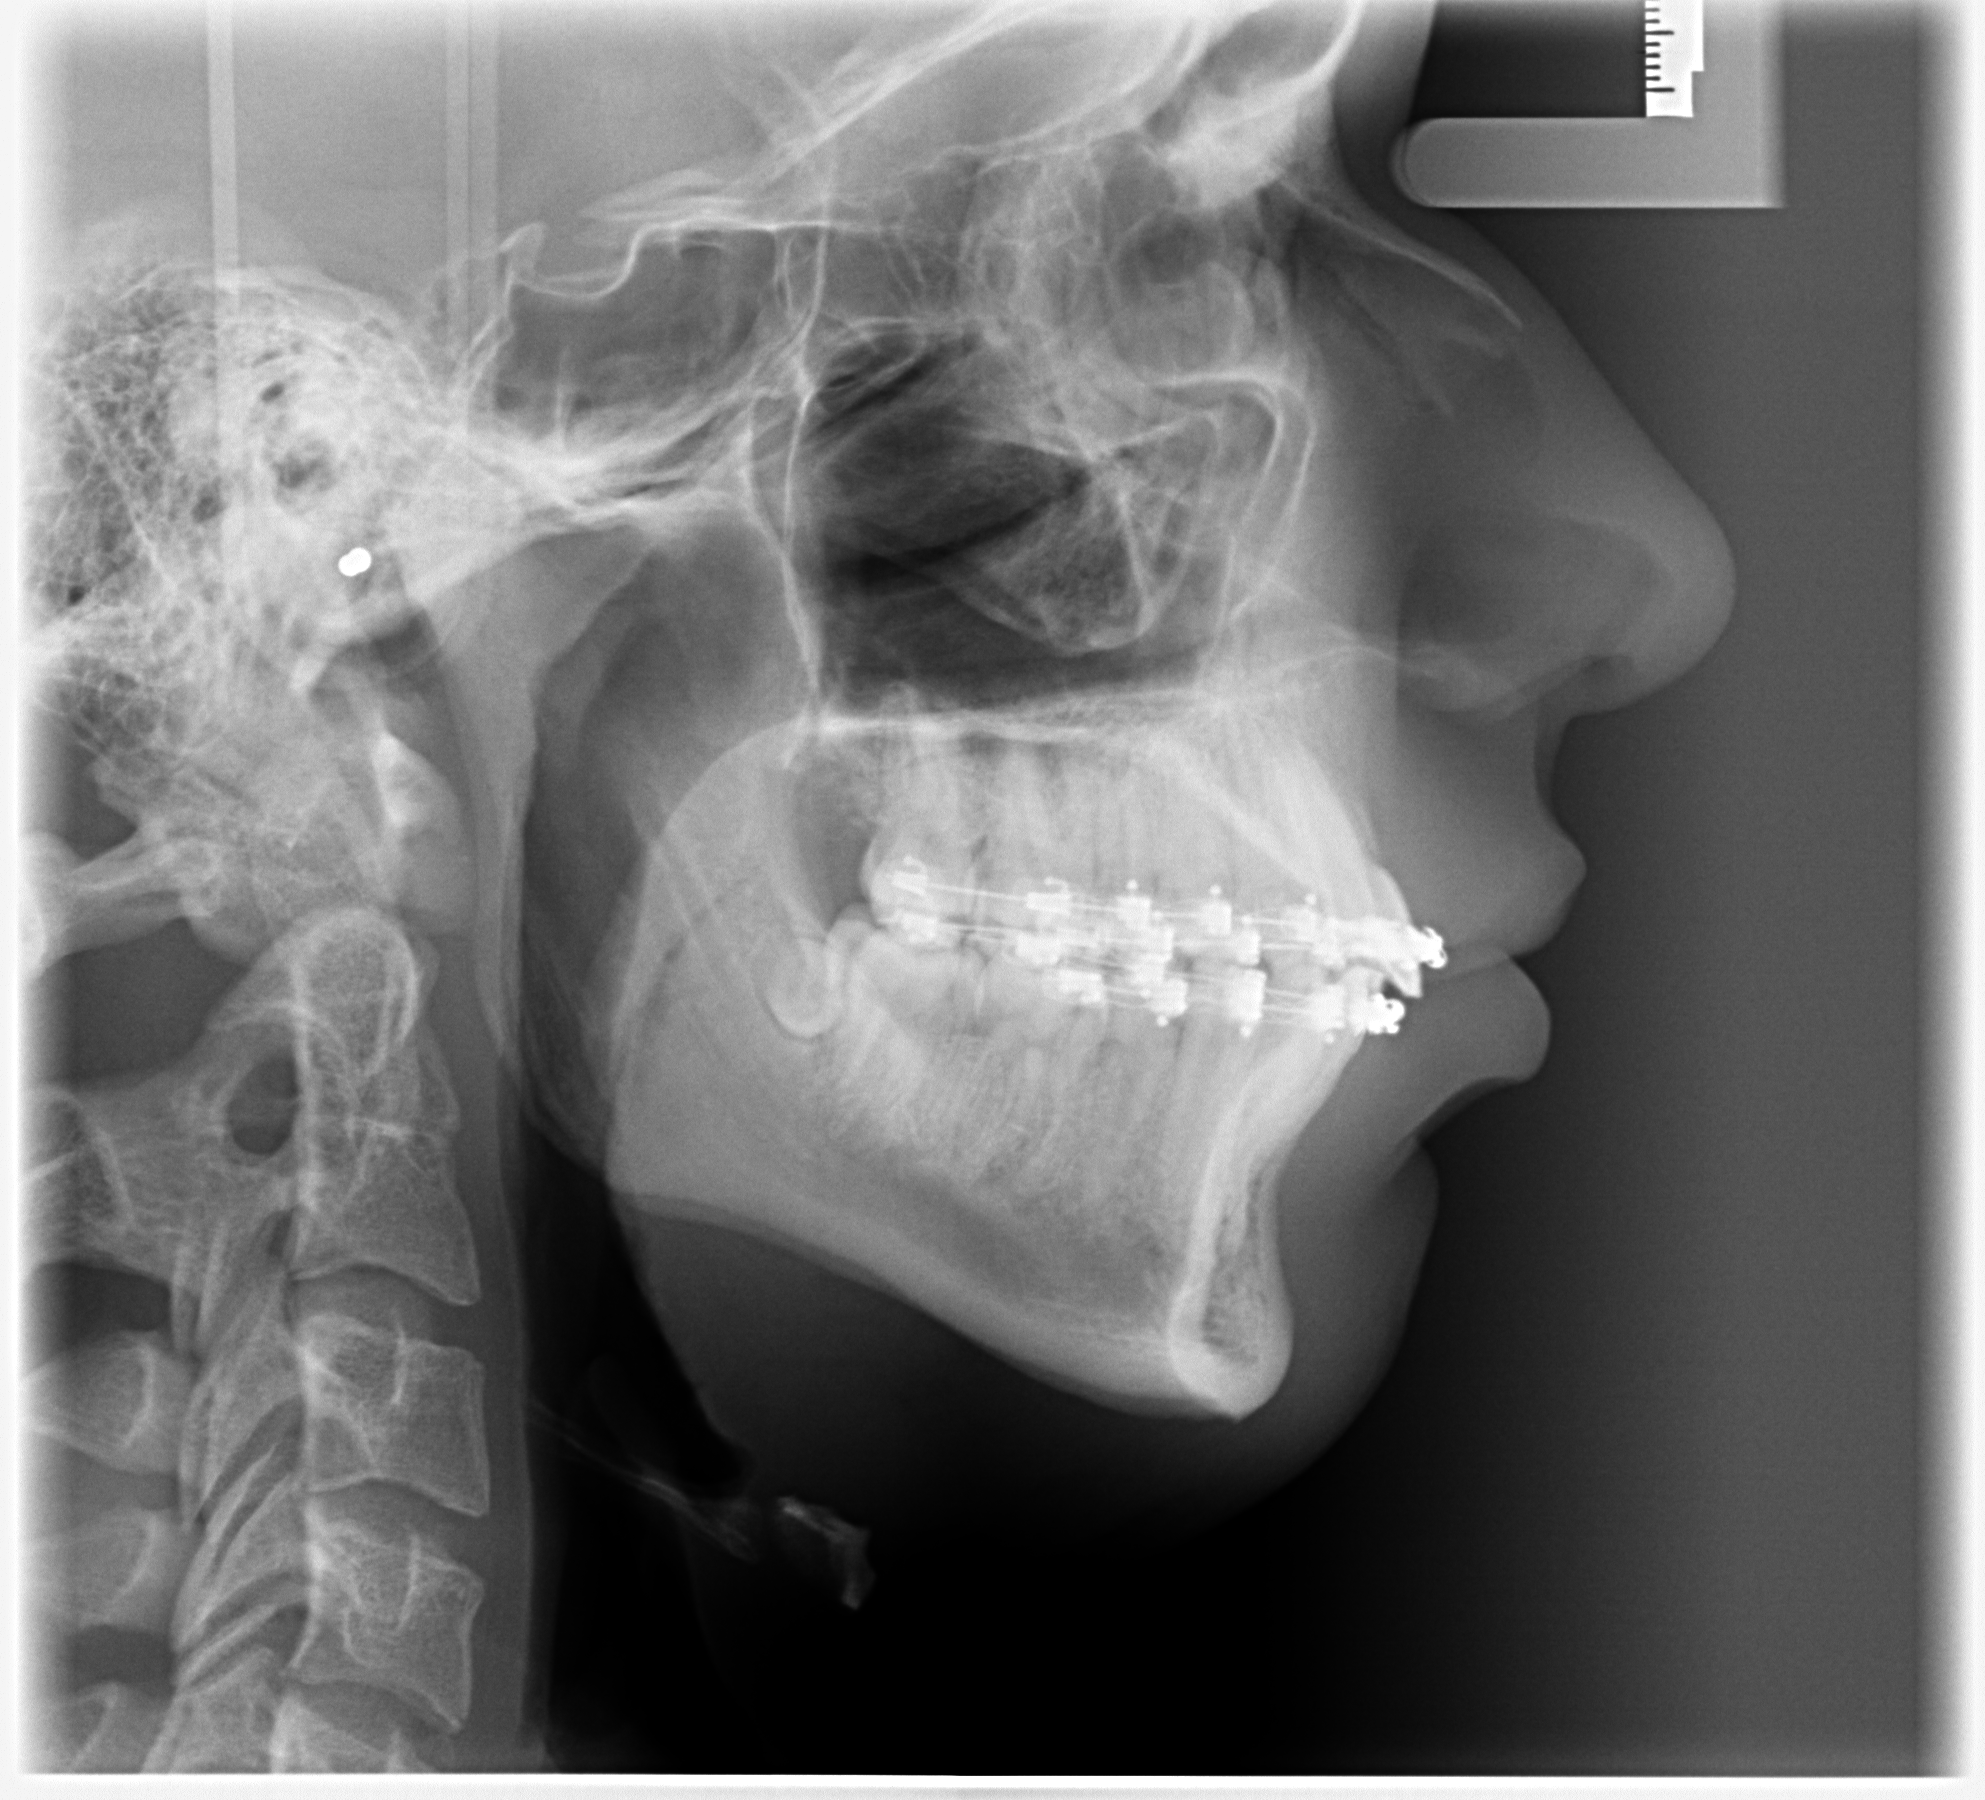

These are my CTs, how big do yall think i will ascend?

Before and after:

• Fabian_Noah_Luca_07022026_094045.png

Fabian_Noah_Luca_07022026_094045.png

2.4 MB · Views: 0